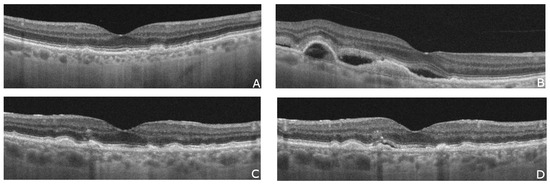

| Hypo-reflective cavities | Located in both inner and outer neurosensory retina [68]. |

| Disruptions of retinal layers | Disruption of the external limiting membrane (ELM), photoreceptor inner segment–outer segment border, and interdigitation zone—one of the most frequently observed OCT features in patients with idiopathic macular telangiectasia type 2 [68]. |

| Thicker temporal retina | Early subretinal neovascularization may be indicated by a thicker temporal retina compared to nasal fovea without retinal fluid [69]. |

| Hyper-reflective lesions | Thick, hyper-reflective lesions in the outer retina, with highly reflective dots in the inner and the outer nuclear layers [69]. |

| Hyperreflective middle retinal layer (MRL) | Loss of Müller cells in the perifoveal region may contribute to increased hyperreflectivity of MRL [70,71,72]. In type 2 MacTel, hyperreflective MRL in the perfoveal region was recognized as the most frequent early OCT finding [71]. |